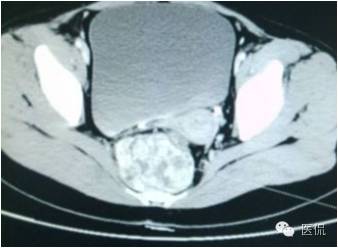

增强静脉期(CT值62HU)